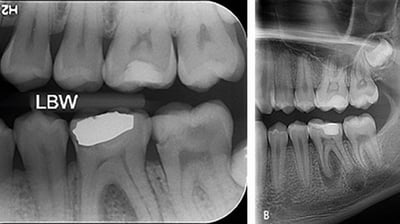

Radiografii intraorale

Aceste radiografii sunt realizate cu senzori intraorali și oferă imagini detaliate ale unor zone specifice ale gurii, precum un singur dinte sau rădăcinile acestuia.